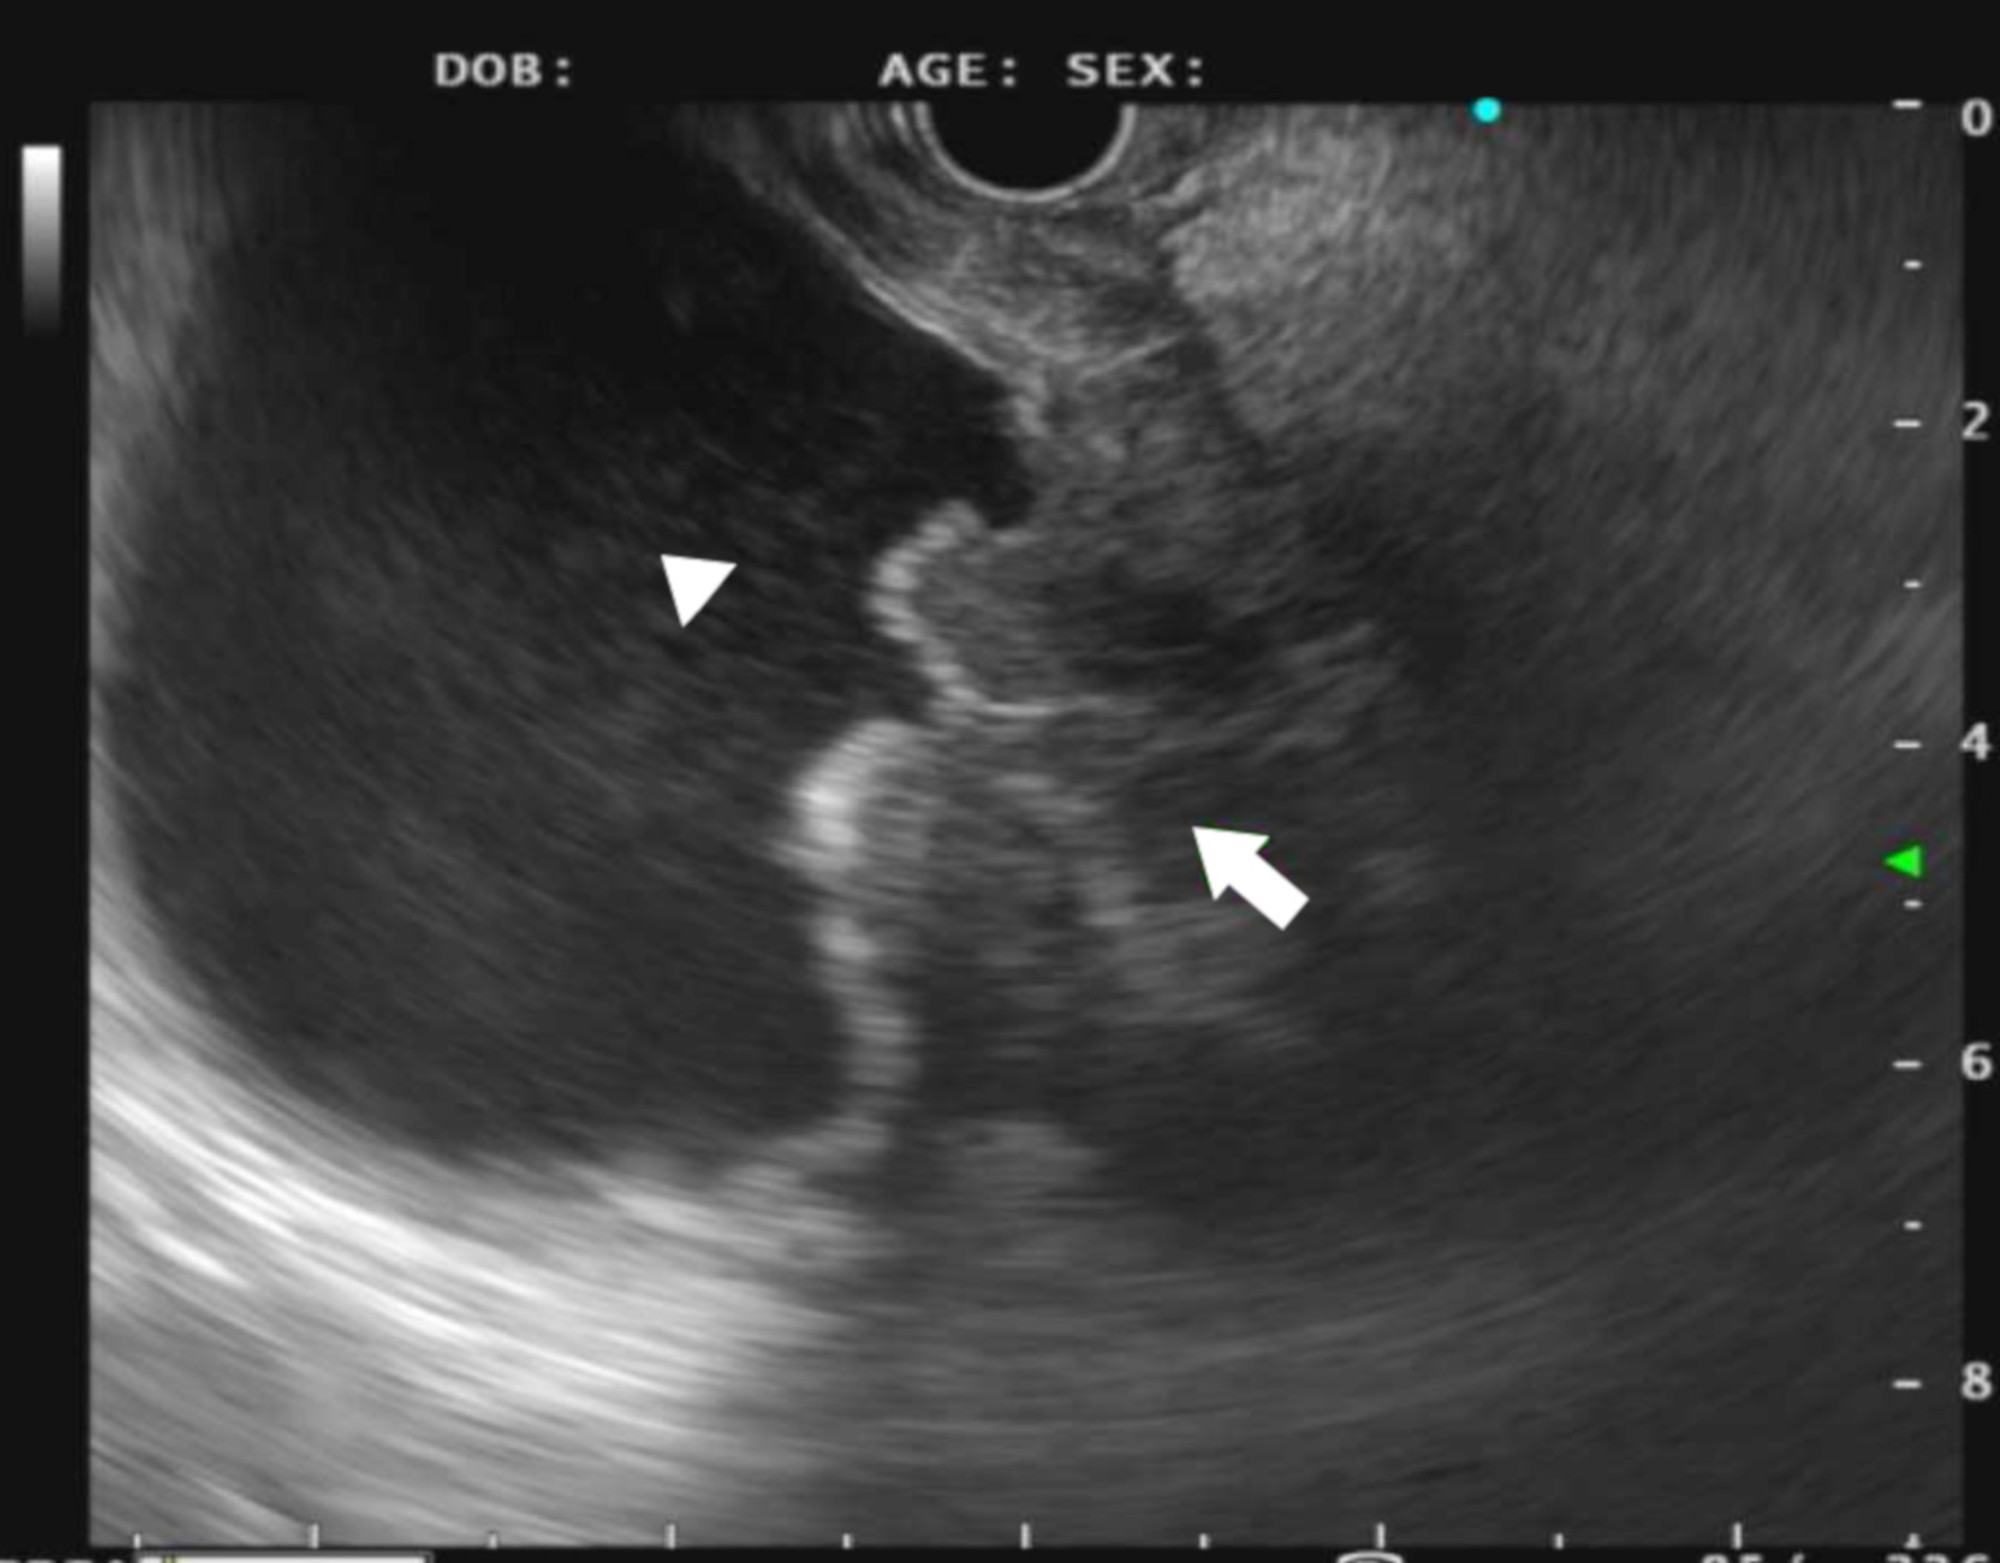

Mo1335 Magnifying Endoscopy With Narrow Band Imaging of Early Gastric Endoscopy Detect Stomach Cancer this test is called a gastroscopy (a type of endoscopy). learn how your gp will refer you to hospital for an endoscopy, and what further tests you may have to confirm or rule out stomach. learn about the signs, symptoms, and risk factors of stomach cancer, and how it is diagnosed with exams, tests, and. It looks. Endoscopy Detect Stomach Cancer.